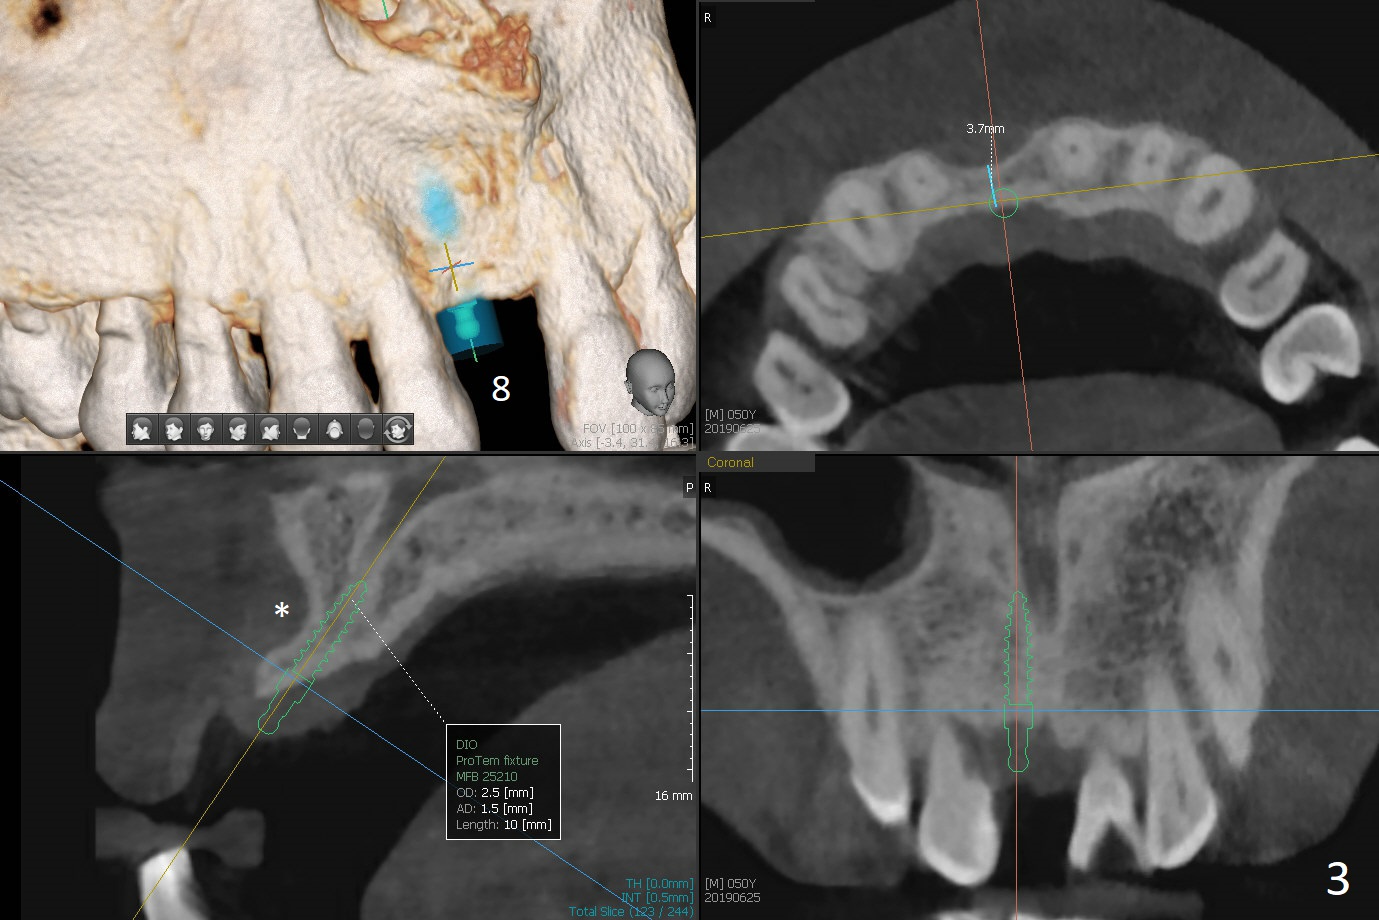

A 50-year-old man loves chewing bone and crab leg. The tooth #19 was extracted due to fracture 1.5 years ago (Fig.1). To reduce abutment screw loosening, IS guide will be used to create osteotomy, while a Tatum implant will be place initially with the guide (Fig.2). There appears no screw loosening associated with Tatum implants. The ridge at #8 is atrophic; a 2.5x10 mm Mini-implant will be placed palatal (Fig.3). The mesiopalatal defect (Fig.4 (lingual view) *) will be bone grafted after implant placement. Incision will be made after the 1st drill for access. The guide will be made with gingival clearance. A piece of 6-month membrane will be cut with a hole buccally to cover the bone graft and slide through the implant.